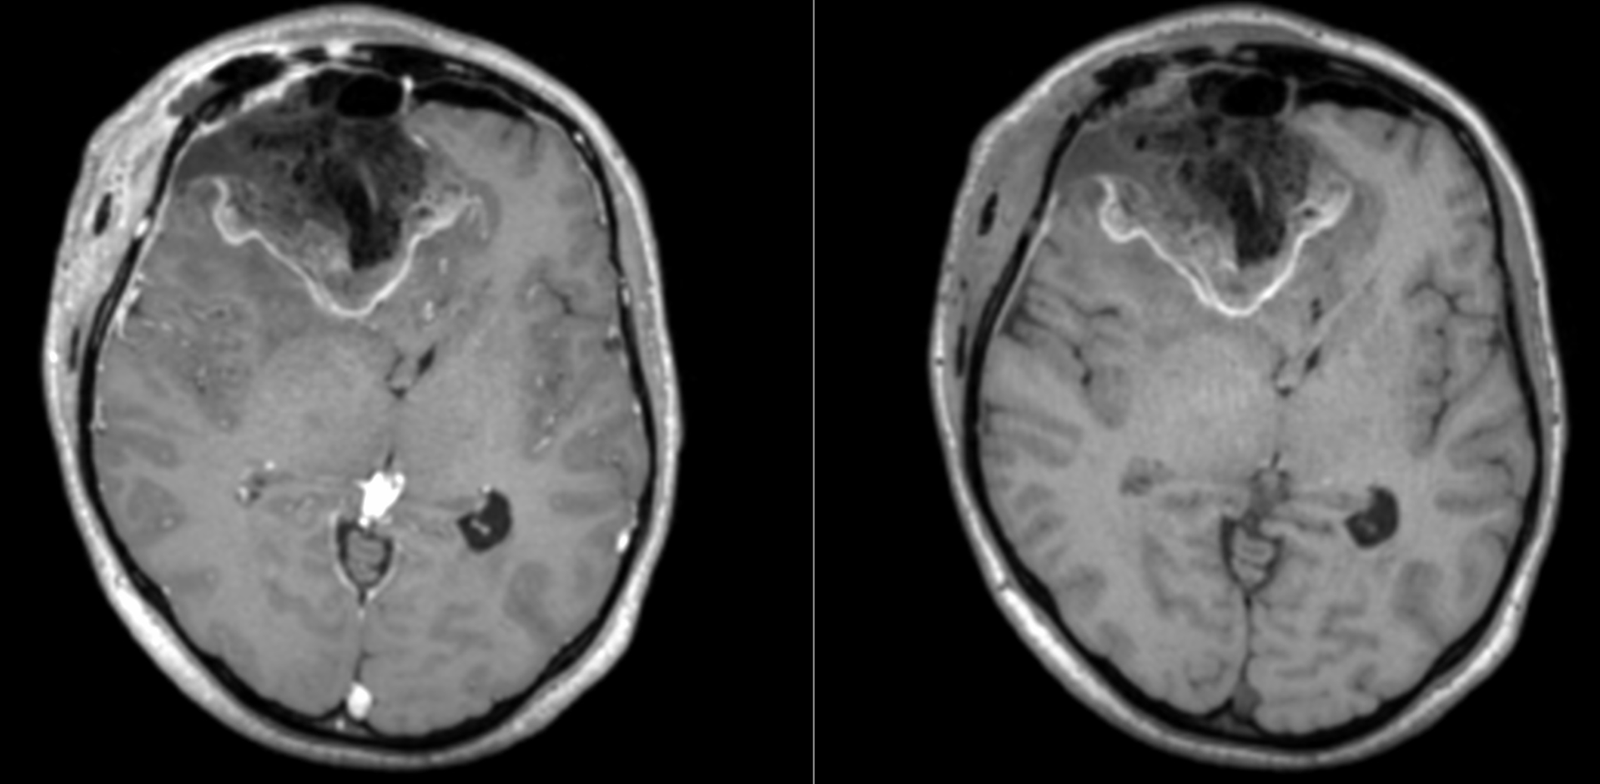

Se reface imagistica – de aceasta dată RMN cerebral cu contrast – și se constată prezența unei tumori cerebrale infiltrative de cca 7/7/6 cm, în cea mai mare parte negadolinofila, hipo-T1, hiper-T2 și FLAIR, cu zone hemoragice la interior și efect de masă important – deplasarea structurilor liniei mediene cu 2 cm, hernie de girus cinguli și hidrocefalie internă prin obstrucția formen Monro – imagine sugestivă pentru un gliom de grad înalt, cel mai probabil glioblastom.